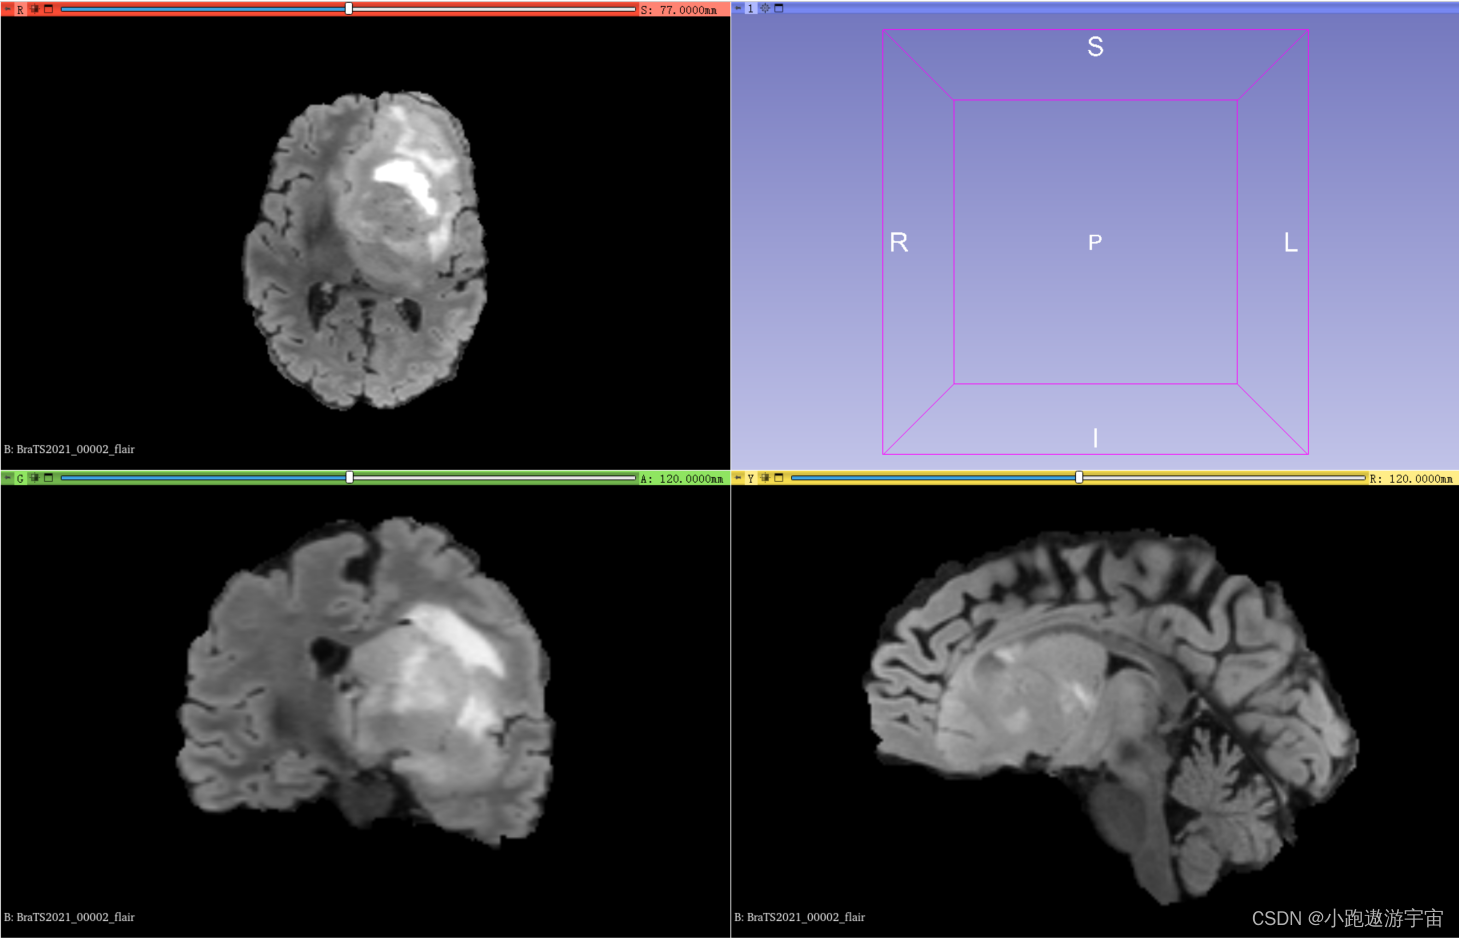

BRATS 2021数据集是一个医学图像分割数据集,该数据集由2000例患者脑部MRI(核磁共振成像)扫描构成。其中训练集有1251例、验证集219例、测试集530例,每例MRI扫描有4个模态的3D图像。其中训练集是包含3D图像和分割标签的,而验证集和测试集则不包含分割标签,验证集被用于公共排行榜,测试集不公开,用作参赛者的最终排名评测。

训练集其中一例MRI扫描(包含4个模态的3D图像以及1个共享标签)

FLAIR(Fluid Attenuated Inversion Recovery)成像:这种成像方式通过将T2序列与T1序列结合起来,使用反转恢复脉冲序列,增强了病变和脑脊液的对比度。FLAIR序列主要用于显示肿瘤、炎症和其他异常组织。

BraTS2021_00002_flair.n